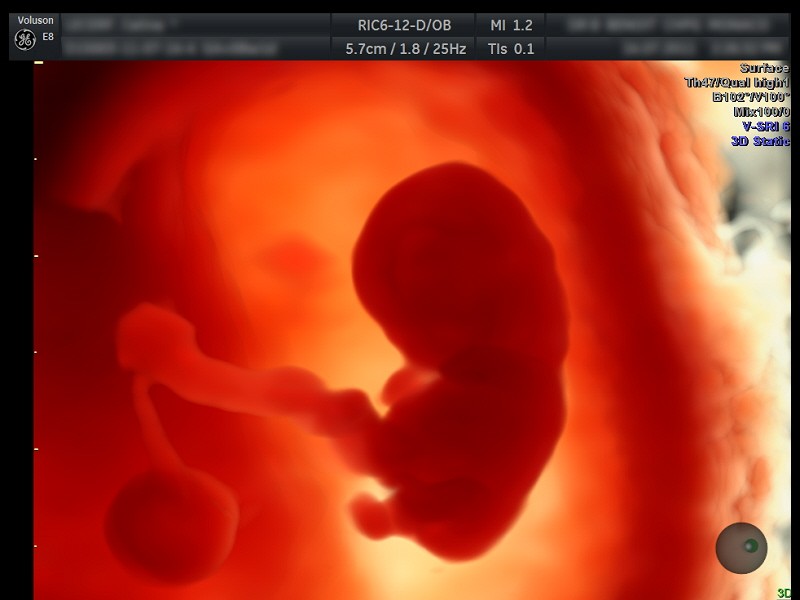

Kurzusainkon a legújabb szakmai elvárásoknak megfelelő elméleti és gyakorlati ismereteket adjuk át a résztvevőknek. Modern ultrahangvizsgálati eszközeinkkel, fantomon és élő modelleken sajátíthatják el a vizsgálati módok gyakorlati fogásait. A képzés tematikájába tartozik a vizsgálati módszertan, az ultrahangos képalkotás 2D-től az 5 D-ig, a szükséges szoftverek használata és a patológiás eltérések tematikus áttekintése. A tanfolyam résztvevőit a kurzus alatt segítjük a nemzetközi portálokon való regisztrációban, így a világ szülészet-nőgyógyászati ultrahangvizsgálók aktuális trendjébe kapcsolódhatnak be. Az első trimeszteri szűrés kurzusnapon minden résztvevőt segítünk megszerezni az FMF akkreditációt nyaki redő mérésre, orrcsont megítélésére, ductus venosus és arteria uterina flowmetriára és tricuspidalis regurgitációra. A magzati szívultrahangos napon Dr. Ladányi Anikó gyermekkardiológus főorvos, magzati szívultrahang specialista vezet be mindenkit a módszertanába, és mutatja be páratlan anyagát.